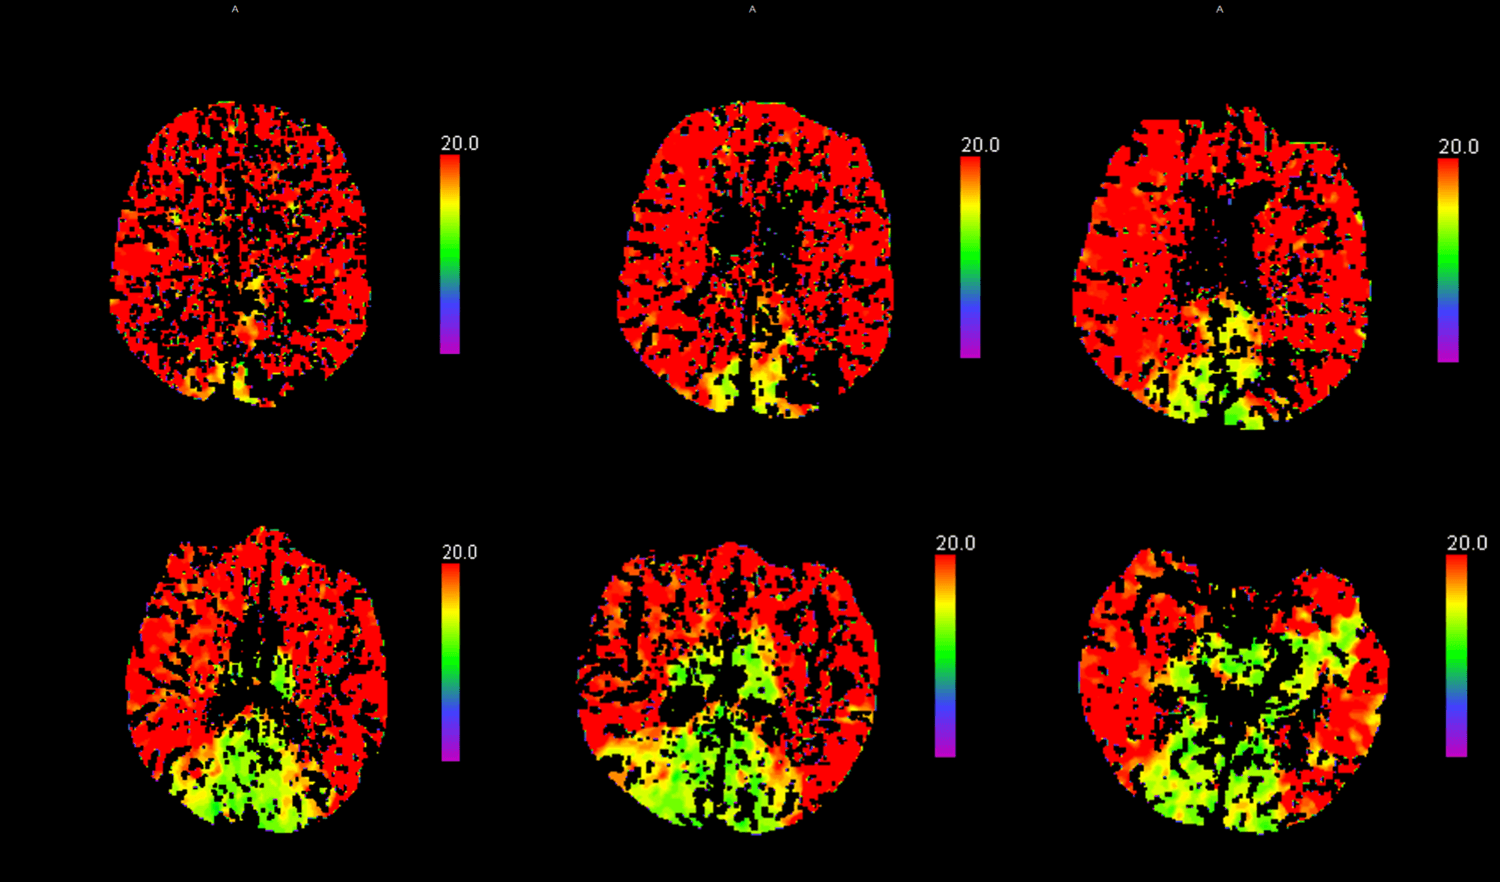

El estudio de la perfusión cerebral pone de manifiesto.

Un extenso territorio de retraso en mapas de tiempo a nivel de la totalidad del territorio de ambas carótidas con relativa área respetada a nivel de la circulación posterior.

Los mapas de volumen presentan algunas zonas parcheadas de menor perfusión.